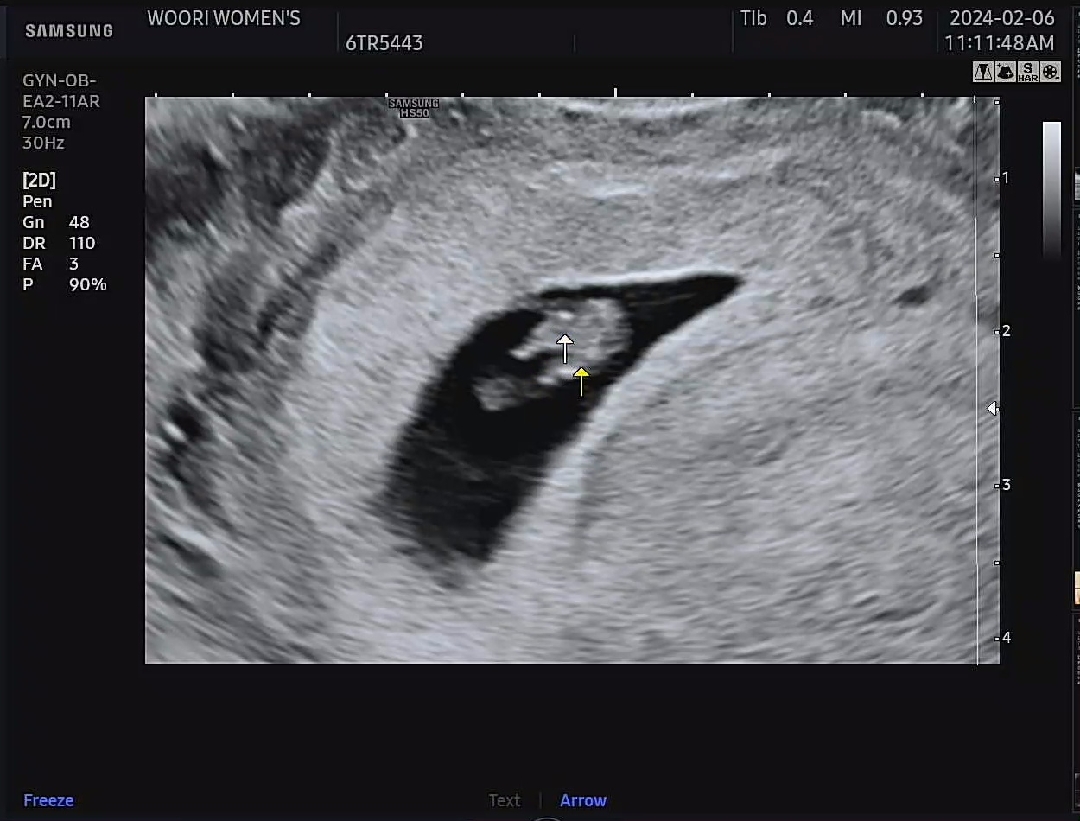

8주차 걱정태산

6주차에 임신을 알고 일이 엄청 힘든일(공장급)이라 걱정이 태산이었는데 병원을 가볼까생각하다 8주차 병원갈때까지만이라도 조심하자는 생각에 7주차 일을 그만두고 안정을.... 엄청 걱정하고 설레는 마음으로 남편과 함께 병원다녀왔어요~~~ 정말 다행히도 아가는 건강하고 심장소리도 우렁찼어요^^ 남편이랑 처음으로 병원갔었는데 남편눈에는 꿀이 뚝뚝♡♡♡ 하리보같은 아가보고 팔조금 다리조금 나온거 보고왔답니다~~(닭다리같이 두다리 길쭉~~) 용띠맘분들 너무 걱정하지마시고 아가를 믿어봐요~ 아가도 엄마 걱정에 불안하답니다!! 살찔걱정하지마시고 맛난음식 건강한음식 많이 드세요🥹